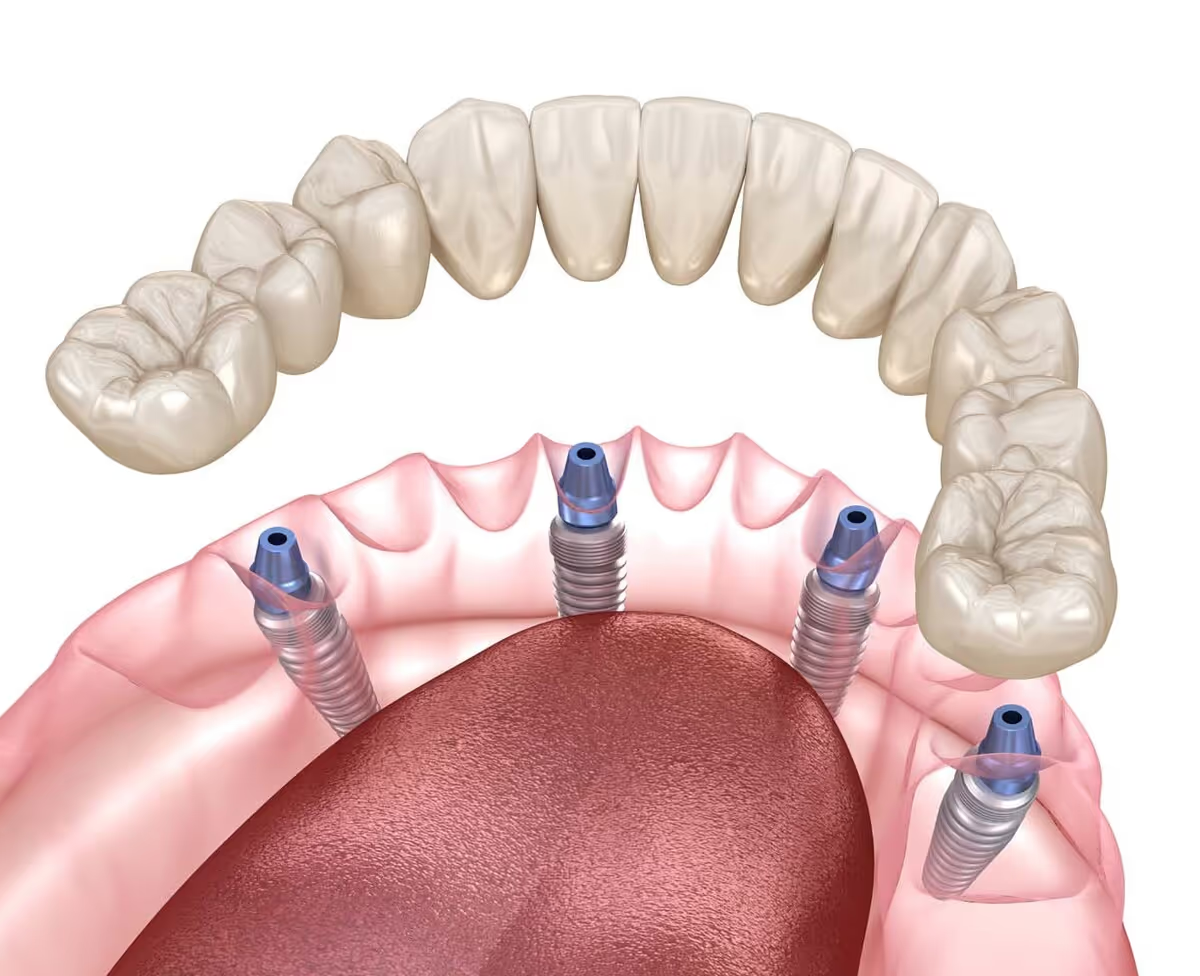

How Implant-Supported Dentures Work

- Implant Placement: Titanium posts are surgically placed in the jawbone to serve as anchors.

- Healing & Integration: The implants fuse with the bone in a process called osseointegration.

- Attachment of Denture: A custom denture is designed to connect securely to the implants.

Most patients require 4–6 implants for a full arch of dentures.